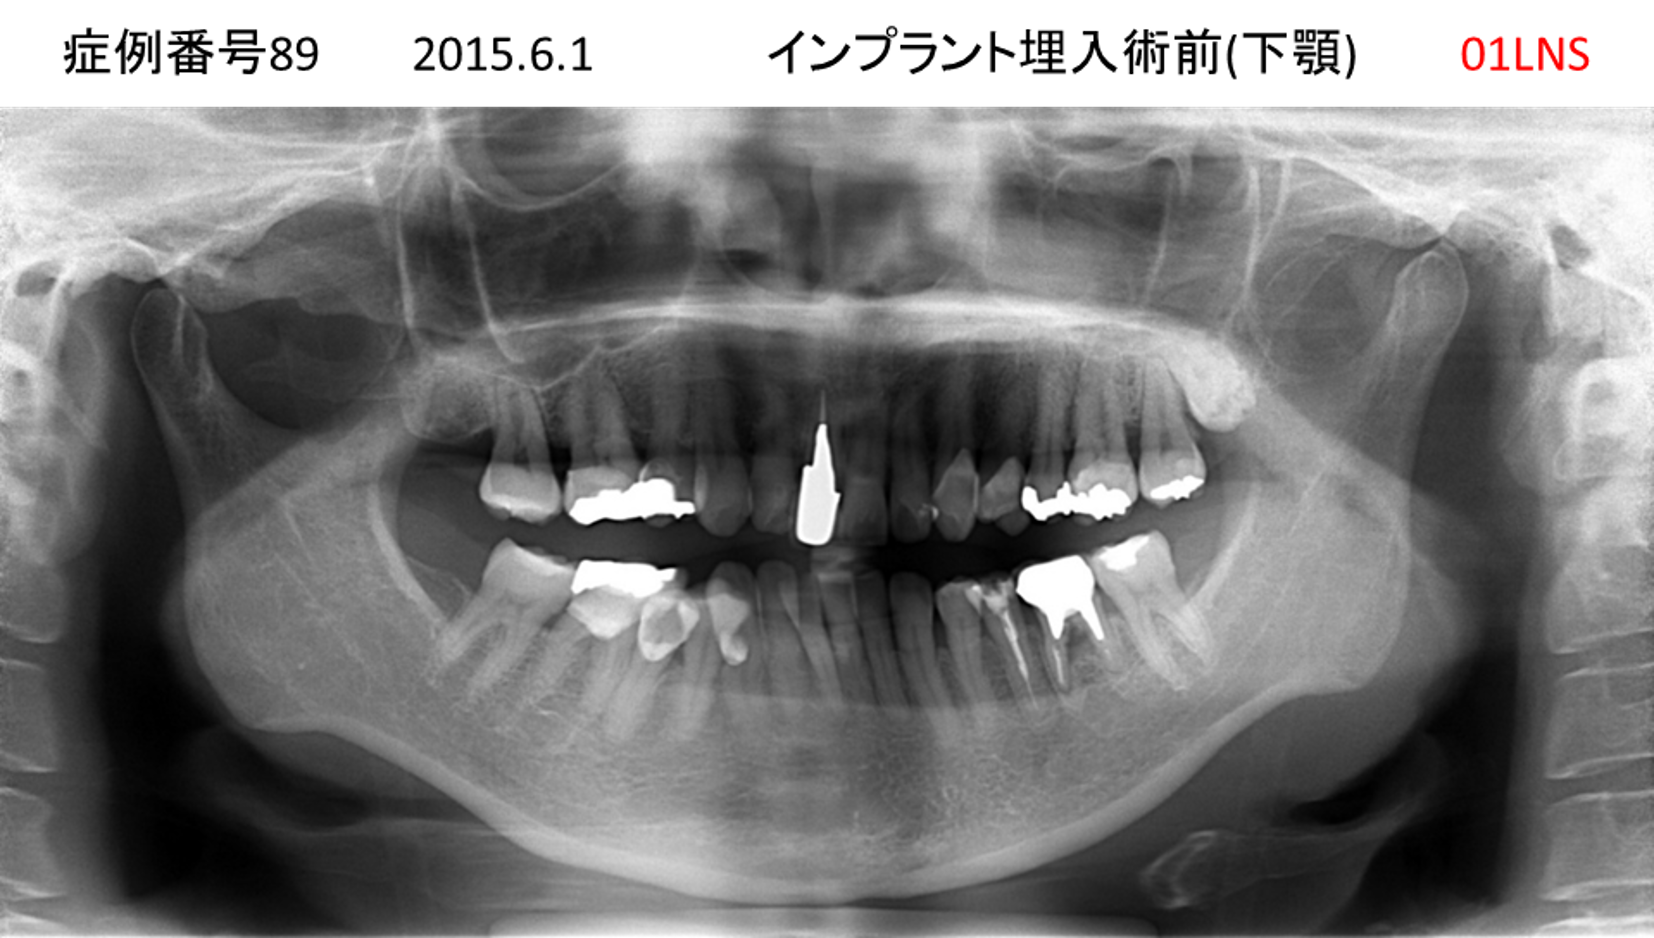

左下の奥歯が痛い患者様のインプラント症例

| 治療名称 |

インプラント |

| 治療費用 |

215万円+税 |

| 治療期間 |

5か月 |

| 患者さんの症状(主訴) |

左下の奥歯が痛い。 |

| 治療内容 |

| 治療結果 |

痛み無く、噛める。 |

| 治療の注意点(リスク/副作用) |

インプラントが壊れたら再治療が必要 |